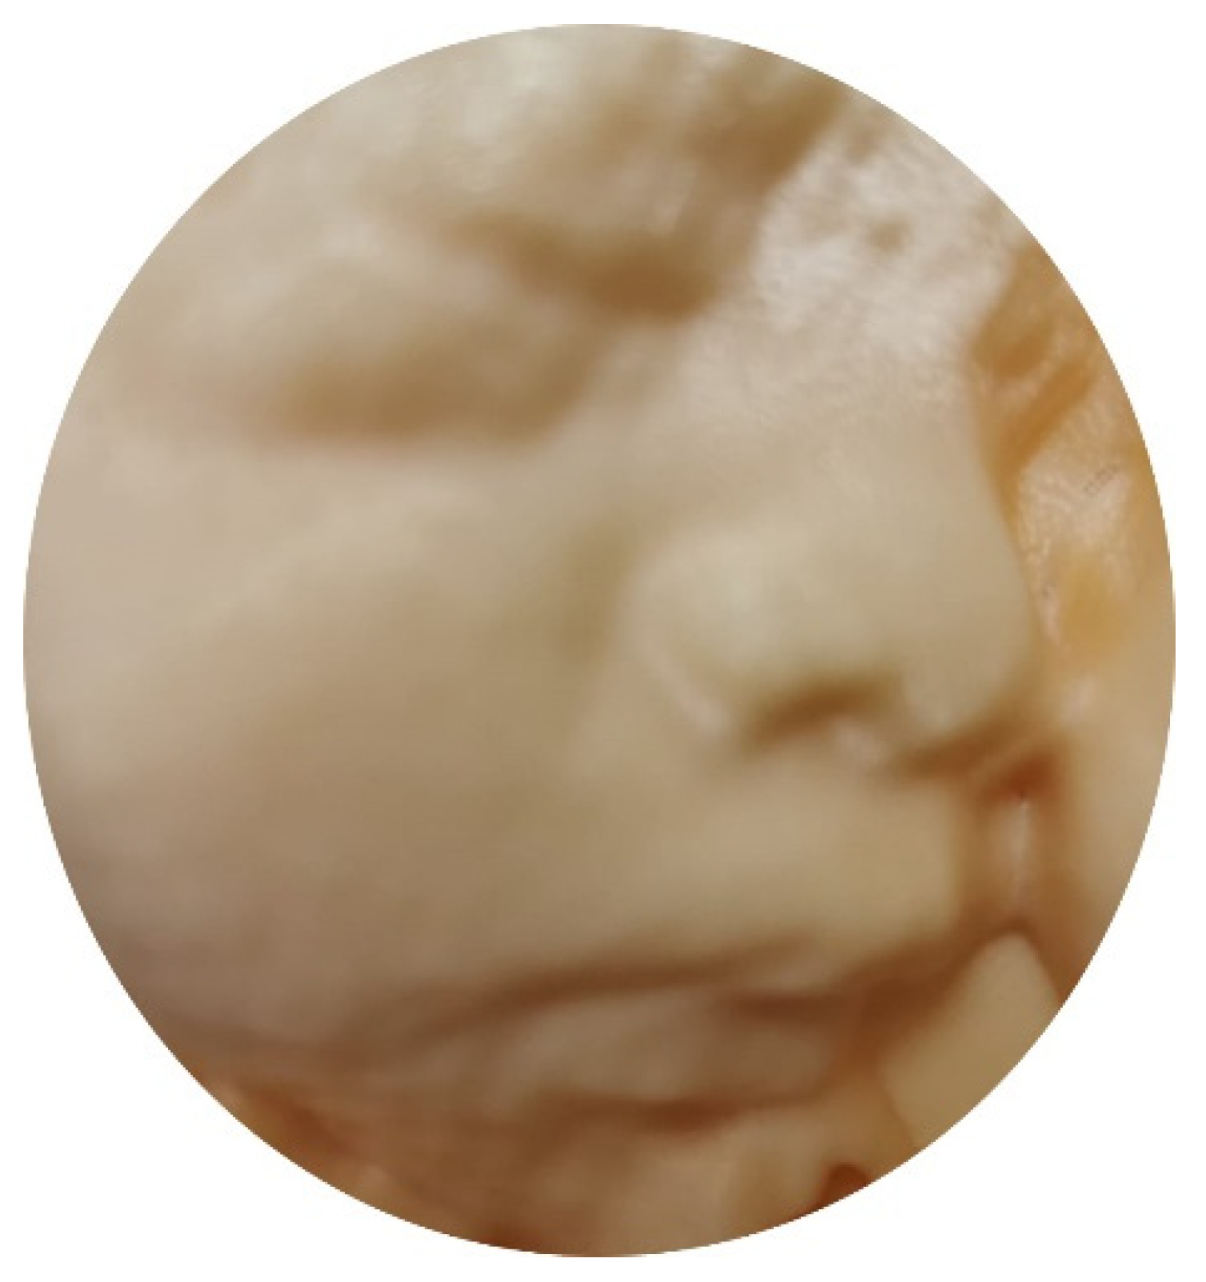

5.3. 3D Ultrasound Examination of Face, Limbs, and Other Structures

- Tutschek, B.; Blaas, H.K.; Abramowicz, J.; Baba, K.; Deng, J.; Lee, W.; Merz, E.; Platt, L.; Pretorius, D.; Timor-Tritsch, I.E.; et al. ISUOG 3D Special Interest Group. Three-dimensional ultrasound imaging of the fetal skull and face. Ultrasound Obstet. Gynecol. 2017, 50, 7–16. [Google Scholar] [CrossRef]